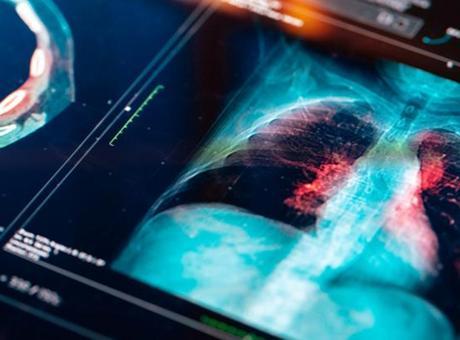

Akciğer kanseri neden sigara içmeyenlerde görülüyor?

Akciğer kanserinin en sık görülen kanser türü olduğunu Göğüs Cerrahisi Uzmanı Dr. Fatih Gürler, "Maalesef akciğer kanseri artık sigara içmeyenlerde ve özellikle kadınlarda da görülme sıklığı artmaya başladı" dedi.

Akciğer kanserinin en sık görülen kanser türü olduğunu Göğüs Cerrahisi Uzmanı Dr. Fatih Gürler, "Maalesef akciğer kanseri artık sigara içmeyenlerde ve özellikle kadınlarda da görülme sıklığı artmaya başladı" dedi.